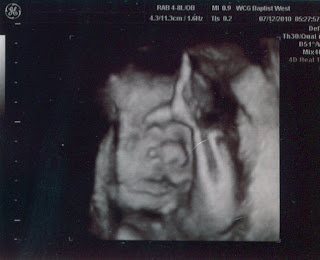

Now you know why I’ve been so quiet here lately: It’s been…